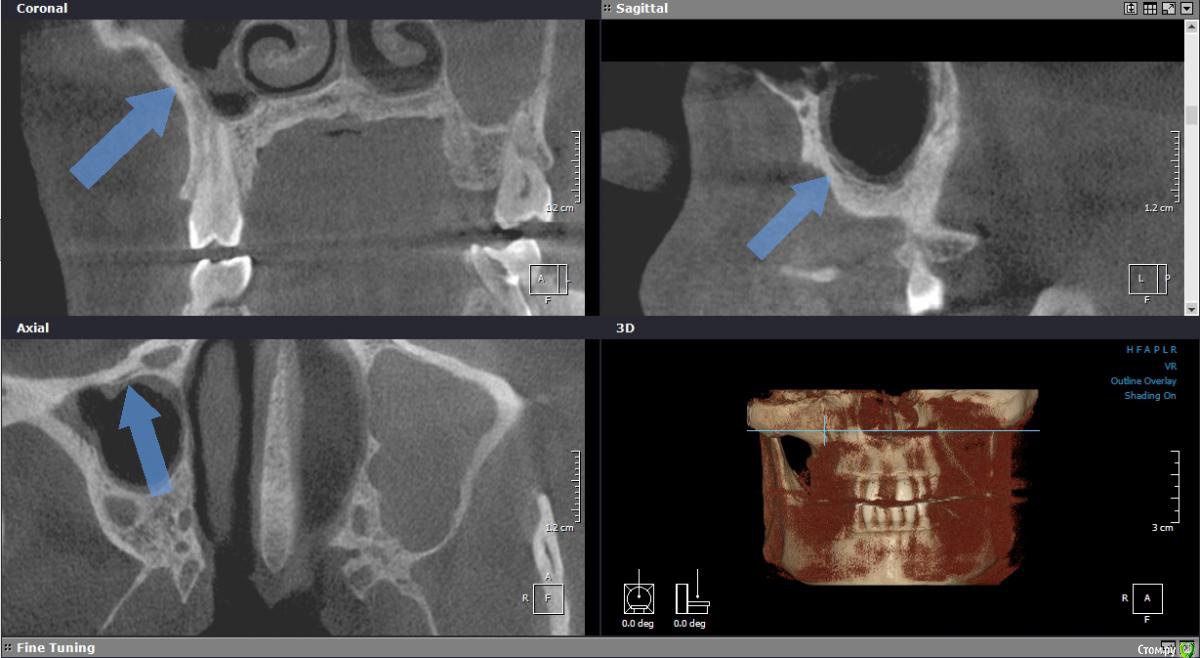

Bier Опубликовано 7 сентября, 2017 Поделиться Опубликовано 7 сентября, 2017 закрытый тут самое то. В таких толстых стенках надо опасаться прохождения крупного сосуда. Смотрите КТ внимательнее, а так ничего особенного. Ссылка на комментарий

Iv_serg Опубликовано 8 сентября, 2017 Автор Поделиться Опубликовано 8 сентября, 2017 закрытый тут самое то. В таких толстых стенках надо опасаться прохождения крупного сосуда. Смотрите КТ внимательнее, а так ничего особенного.Сосуд конечно же есть, но вроде некрупный(на первых двух срезах отметил). Еще раз спрошу, как при ЗСЛ работать с таким перепадом(на третьем срезе указал). Ведь фрезой пройти можно до нижнего края, как поднимать кость в области перепада? Ссылка на комментарий

Bier Опубликовано 9 сентября, 2017 Поделиться Опубликовано 9 сентября, 2017 тут лифтинг не нужен. А сосуд там очень крупный!! 1 Ссылка на комментарий